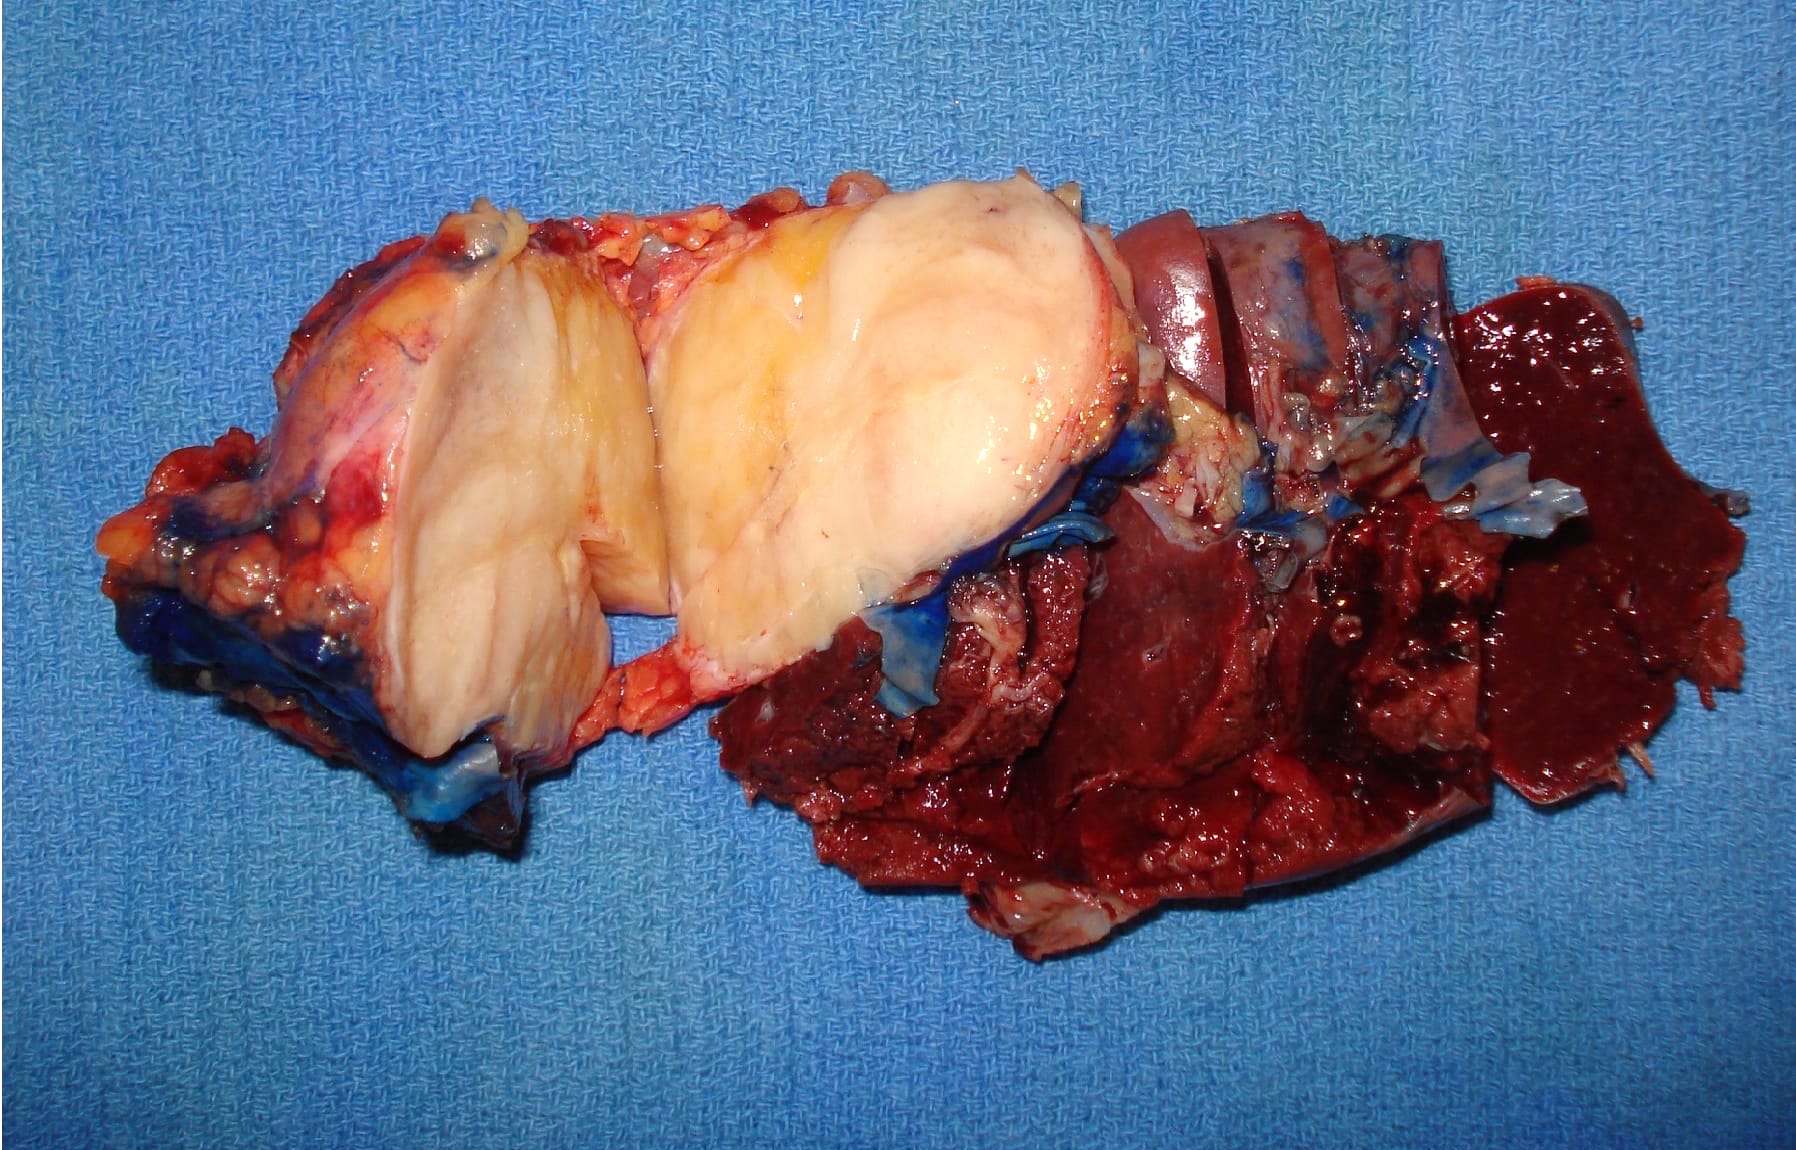

Gross description

- Range from 0.5 to 34.5 cm, with a mean diameter of 6 cm

- Well defined, encapsulated, with variable amount of solid and cystic patterns

- Smaller lesions tend to be more solid but less sharply circumscribed

- Larger tumors demonstrate a fibrous pseudocapsule and have a variegated and friable cut surface

- Cystic degeneration and hemorrhage are common findings in larger specimens

- Rarely, may extend into adjacent structures, such as duodenum

- Reference: Arch Pathol Lab Med 2020;144:829

Gross images

Contributed by Omid Savari, M.D., Dr. Andreas Schulz, Manfred Stolte, M.D., Dr. Helmut Luchtrath, Wei Chen, M.D., Ph.D., Nakul Anush Ravish, M.B.B.S. and Case #121